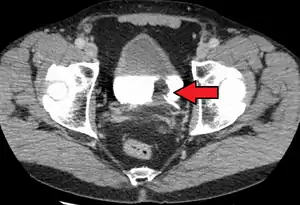

If invasive or high grade (includes carcinoma in situ) cancer is detected on TURBT, an MRI and/or CT scan of the abdomen and pelvis or urogram and CT chest should be conducted for disease staging and to look for cancer spread (metastasis).[56] Increase in alkaline phosphatase levels without evidence of liver disease should be evaluated for bone metastasis by a bone scan.[57] Although 18F-fluorodeoxyglucose (FDG)-positron emission tomography (PET)/CT has been explored as a viable method for staging, there is no consensus to support its role in routine clinical evaluations.[54]

The most common sites for bladder cancer metastases are the lymph nodes, bones, lung, liver, and peritoneum.[78] The most common sentinel lymph nodes draining bladder cancer are obturator and internal iliac lymph nodes. The location of lymphatic spread depends on the location of the tumors. Tumors on the superolateral bladder wall spread to external iliac lymph nodes. Tumors on the neck, anterior wall and fundus spread commonly to the internal iliac lymph nodes.[79] From the regional lymph nodes (i.e. obturator, internal and external lymph nodes) the cancer spreads to distant sites like the common iliac lymph nodes and paraaortic lymph nodes.[80] Skipped lymph node lesions are not seen in bladder cancer.[79]